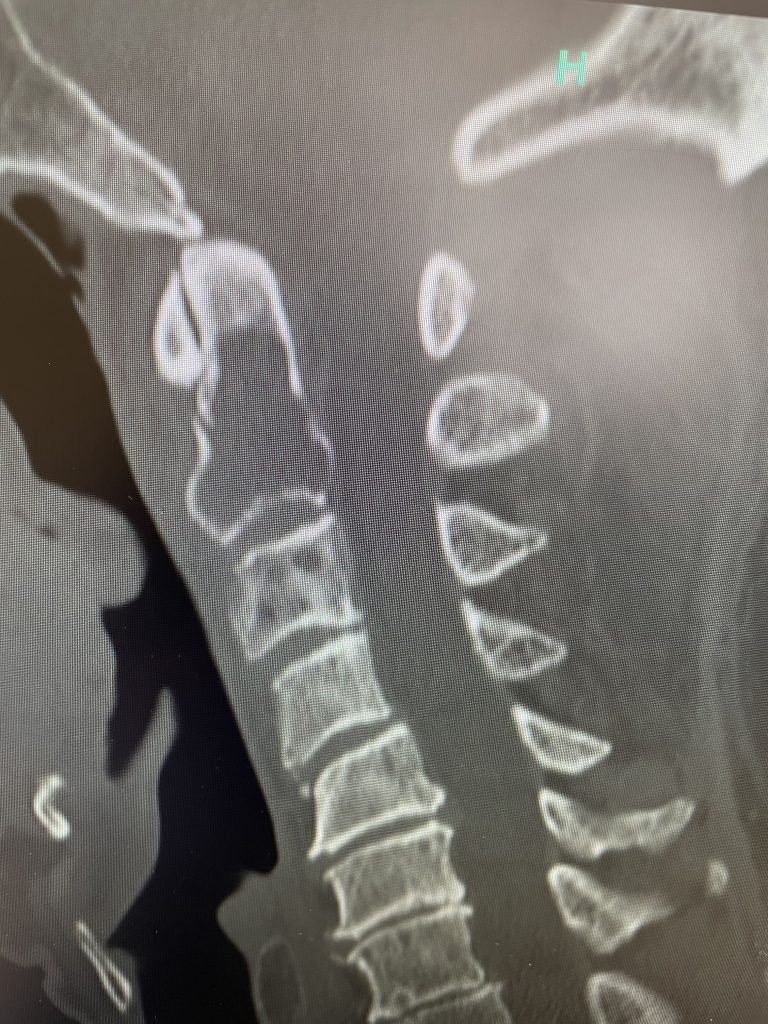

Figure 1: Sagittal T2-weighted MRI demonstrating a kyphotic cervical spine with C4-6 disc collapse with anterior osteophytes causing cord compression

Here is the case of a 51 year-old female who had a ten year history of severe neck pain with severe right arm pain, numbness, and weakness. She weighed over 300 pounds. She had failed all means of conservative management including medicines, physical therapy, chiropractic care, and epidurals. MRI demonstrated a reverse of the normal curvature of the cervical spine with large disc osteophyte complexes compressing the spinal cord (Fig 1). The C4-5 disc osteophyte was larger causing severe anterior compression of the spinal cord, worse on the right side (Fig 2). This correlated with the patient’s clinical findings. Therefore surgery was recommended. Patient underwent an anterior cervical discectomy and fusion with a plate from C4-C6. We were able to get her into a good position. Although there was a very deep exposure through the fat layer, it was not too bad to expose the face of the spine (Fig 3). Because there is less muscle, tissue planes open up actually easier sometimes particularly in women because of a relative decrease in muscle mass. The same goes for exposure of the lumbar spine. The majority of “herniated discs” in the cervical spine are actually bony protrusions we call osteophytes. After you clear away all the other cartilage that is the soft part of the disc, the way to get rid of that C4-5 osteophyte which acts like a sheet of bone at the posterior aspect of the disc space, is to drill it down to a fine shell and remove it with a special tool. This tool is called a Kerrison and has a very thin footplate that allows a plane between the osteophyte and dura which is being compressed and bites away this bone. The patient had good relief of her symptoms postoperatively.